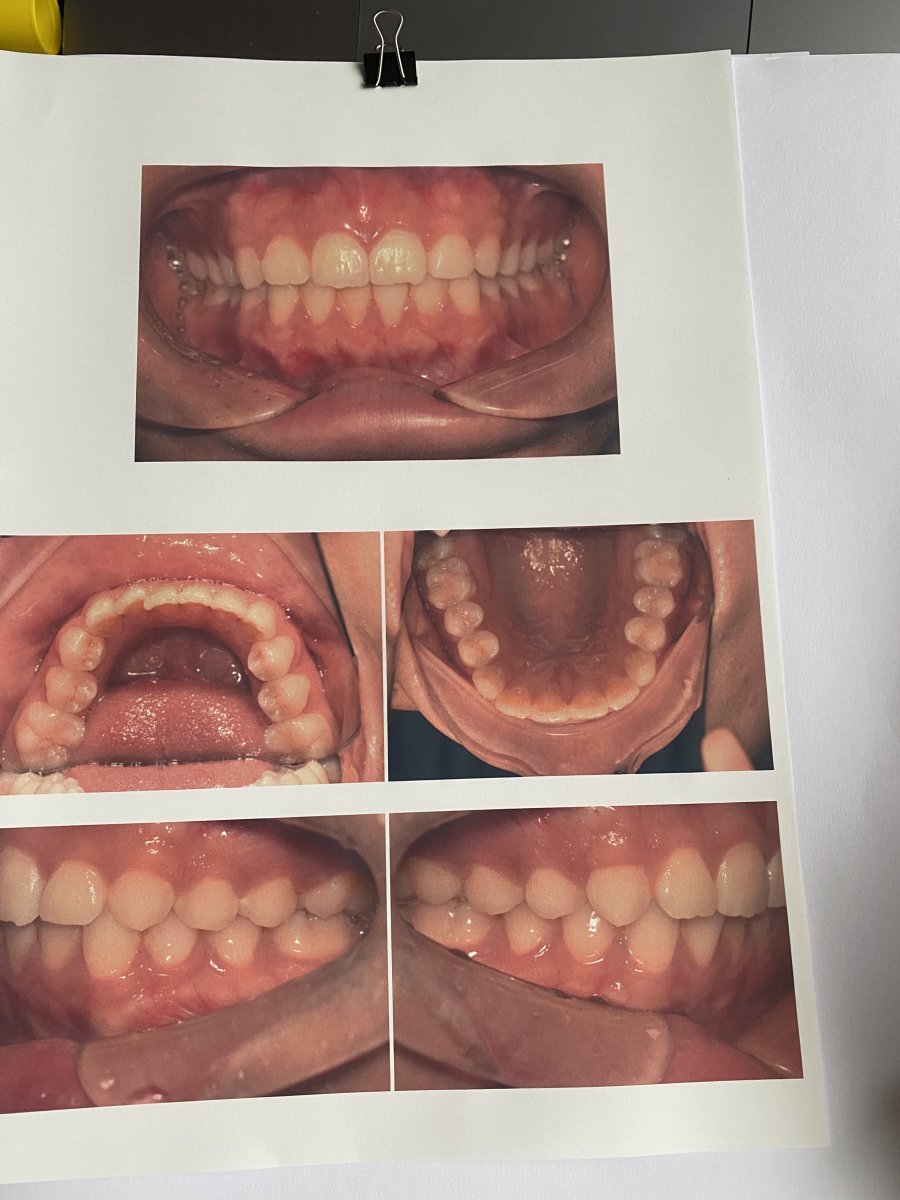

The starting point of this project is me going to see the dentist. I found out the mouth could be a interesting idea to research as a shared space. Here's some visual primary research.

My mouth scanning

kept receipts of seeing the dentist